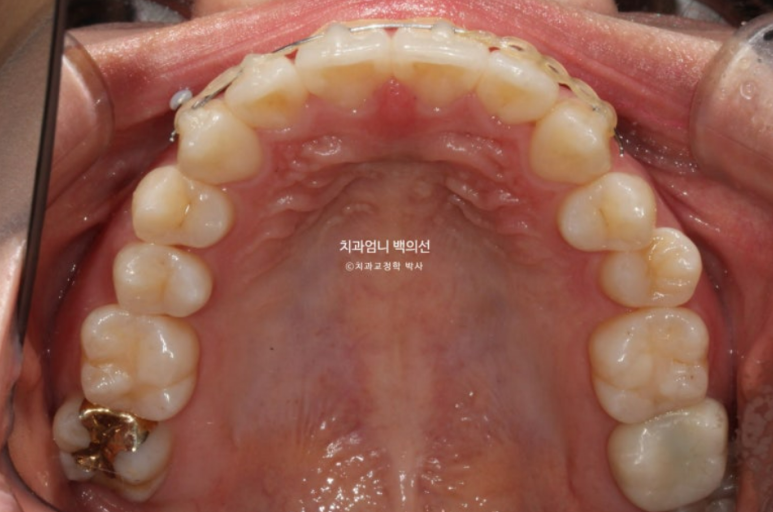

23년 12월 앞니 부분교정을 위해 오신 분입니다.

앞니 두 개가 크기도 하고 내려와 있습니다.

파란 화살표에 작은 어금니 덧니도 보입니다.

아래 앞니가 많이 삐뚭니다.

어금니 교합이 그리 좋은 편은 아니지만 환자분은 씹는데 불편함을 못 느끼는 상태였고 앞니 배열만 원하셨습니다.

앞니 부분교정용 장치 중 MTA 장치를 선택하셨고 치료에 들어갔습니다.